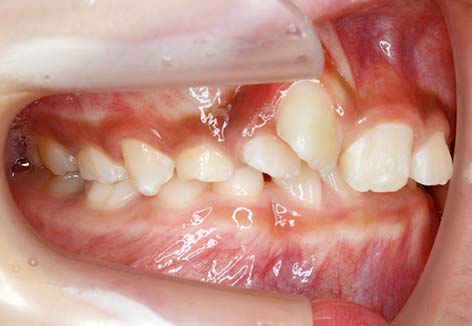

![]() |

⑥臼歯部交差咬合:奥歯の噛み合わせが反対で顎偏位を伴います。写真は、右側臼歯部交叉咬合により、下顎が右側に偏位した症例。 |